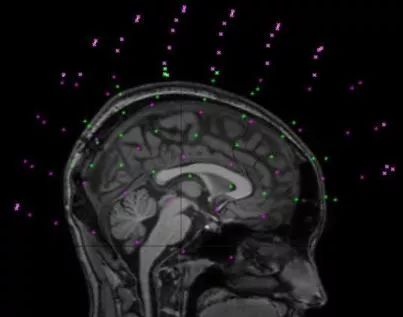

③Multi-modal Analysis: 多模态配准

多模配准常见于医学图像领域,故以多模医学图像配准为例。

由于医学成像设备可以提供关于患者不同信息不同形式的图像(计算机断层扫描CT,核磁共振MRI,正电子发射断层成像PET,功能核磁共振fMRI等)。

基于单种或多种模态图像的配准,可划分为单模态(Single-modality)和多模态(Multi-modality)。

Figure 1 MEG-MRI多模态配准